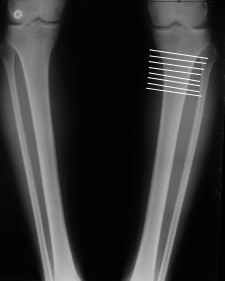

Картинки - в приложении.Будут вопросы - готов ответить.

Ещё картинка - схема. Хотя у Соломина всё написано.

Вот ещё картинки, которые отправлял в Ортопод. Коррекция кривизны и удлинение на 3 см.

4. Если внимательно посмотришь на рентгенограммы, то в зоне перелома малоберцовой кости она втягиваетсмя внутрь, таким образом немного уменьшая объем тканей по внутреннему контуру. Причем чем выше - тем эффектнее. Не надо только совсем высоко лезть - там перонеус. Многих пайциенток это тоже смущает. Так что решаем проблему комплексно. На это, кстати, особо упирает Казбек Кудзаев.